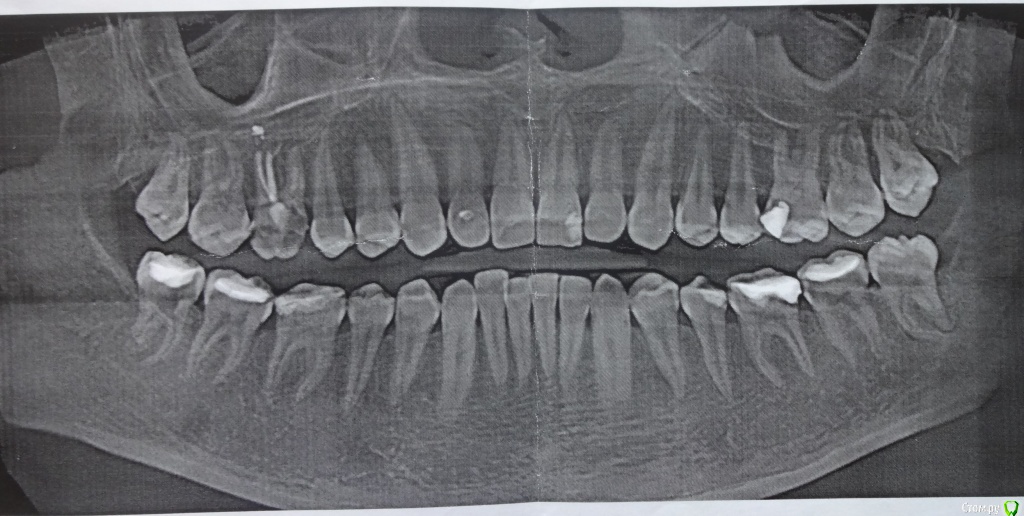

vipi Опубликовано 25 августа, 2015 Поделиться Опубликовано 25 августа, 2015 Здравствуйте.Побывала у ведущих специалистов города по поводу установки брекетов.Мнения разошлись: одни говорят, что нужно удалять восьмерки, другие - делать сепарацию передних зубов. Что предпочтительнее? Нижнее восьмерки, особенно одна у меня с кариесом.У меня достаточно стандартный случай, ближе к легкому. Боковой прикус практически правильный, нижние передние зубы - один сильно выпирает вперед, верхние - анфас правильно, в профиль видно, что один стоит чуток под углом.А еще у меня не очень хорошая шестерка: ее можно восстановить, сделать имплантант, а один отродонт даже предложил 6-ку убрать, на ее место 7-ку, а на место 7-ки 8-ку. Как Вам такой метод лечения в переспективе? Читала, что 8-ки не такие крепкие зубы и смущает, что корни 8-ки и 7-ки будет под наклоном и что впоследствии их будет сдерживать, чтобы они не поехали на место, ретейнер ведь на передние зубы устанавливается? Да и возраст 30 лет, следовательно зубы сформированы. Хотела устанавливать керамику, но один доктор сказал, что у меня мало костной ткани и если меня не смущает, то лучше железные брекеты с замочками Damon, они ведут себя менее агрессивно по отношению к костной ткани.Огромное спасибо заразъяснения. 1 Ссылка на комментарий

vipi Опубликовано 1 сентября, 2015 Автор Поделиться Опубликовано 1 сентября, 2015 ТРГ у меня нет еще, есть томограмма. Ссылка на комментарий

Maverick Опубликовано 1 сентября, 2015 Поделиться Опубликовано 1 сентября, 2015 MaverickОгромное спасибо вам за разъяснение, значит вопрос решен про брекеты: железные, самолигирующие. Вопрос эстетики для меня важен в перспективе, ради результата можно потерпеть, в процессе важнее качество.Да, грамотный врач - это самое главное плюс отсутствие лени у пациента.А еще возник вопрос по снимкам. Лечила зубы и мне сделали панорамный снимок и томограмму (2800 руб), на диске записали, а что еще нужно, а что не нужно из снимков, а то записали еще на диагностику за 4100, может уже не нужно что-то делать, а то девочки на рессепшене ничего не знают. Для того чтобы начать лечение нужен диагностический материал в него входят: ОПТГ ( панорамный снимок ) , ТРГ ( боковая проекция черепа, обычно правая сторона ) , если есть проблемы с ВНЧС ( сустав хрустит , ограниченное открывание рта , асимметрия лица одна и так далее ) , то делают томограмму в трех проекциях сагитальной , фронтальной и аксиальной. Также делают оттиски и отливают гипсовые модели, фото в фас , в профиль , с улыбкой . Внутриротовые фото в окклюзии центральной, при разомкнутых челюстях. Вот весь список Ссылка на комментарий